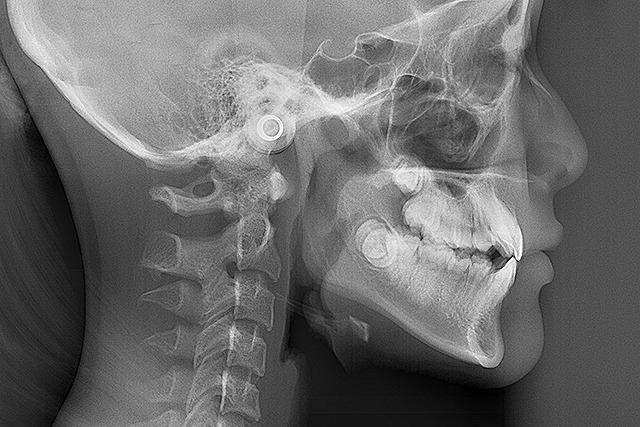

歯や顔のレントゲン、口や顔の写真、歯型など、治療計画に必要なデータを取ります。